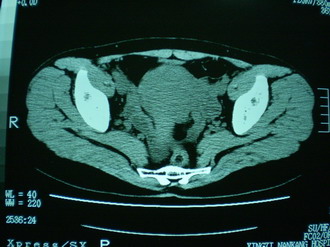

子宫明显前倾,增大,宫颈增大呈分叶状。子宫直肠窝见不规则形水样低密度。(膀胱胀尿不理想)

考虑:1、宫颈部占位;

2、子宫直肠窝少量积液(盆腔炎所致)。

1、前曲子宫,2、宫颈部占位?3、盆腔及右输卵管积液?宫内积血?4、左侧卵巢囊肿。

子宫明显前倾,增大,宫颈增大呈分叶状。子宫直肠窝见不规则形水样低密度。

考虑:1、宫颈部占位(宫颈癌?);

2、子宫直肠窝少量积液。